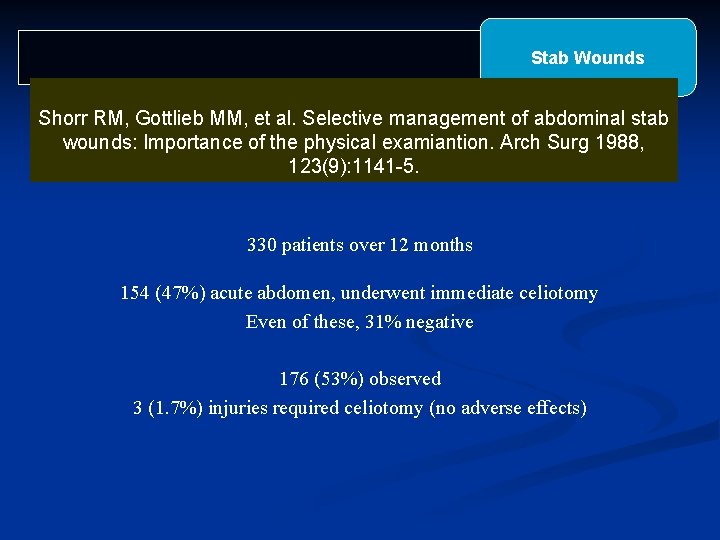

Stab Wounds Shorr RM, Gottlieb MM, et al. Selective management of abdominal stab wounds: Importance of the physical examiantion. Arch Surg 1988, 123(9): 1141 -5. 330 patients over 12 months 154 (47%) acute abdomen, underwent immediate celiotomy Even of these, 31% negative 176 (53%) observed 3 (1. 7%) injuries required celiotomy (no adverse effects)